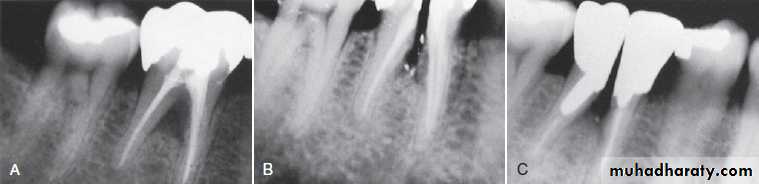

Resection of a root with advanced bone loss. (A) Facial osseous contours. An early grade II furcation is present on the facial aspect of the mandibular first molar, and a class III furcation is present on the mandibular second molar. (B) Resection of the mesial root. The mesial portion of the crown was retained to prevent mesial drift of the distal root during healing. The grade II furcations were treated by osteoplasty. (C) Buccal flaps adapted and sutured. (D) Lingual flaps adapted and sutured. (E) Three-month postoperative view of the buccal aspect of this resection. New restorations were subsequently placed. (F) Three-month postoperative view of the lingual aspect of this resection.

Root Resection

Root resection may be indicated in multirooted teeth with grades II to IV furcation involvement.

may be performed on vital teeth or endodontically treated teeth.